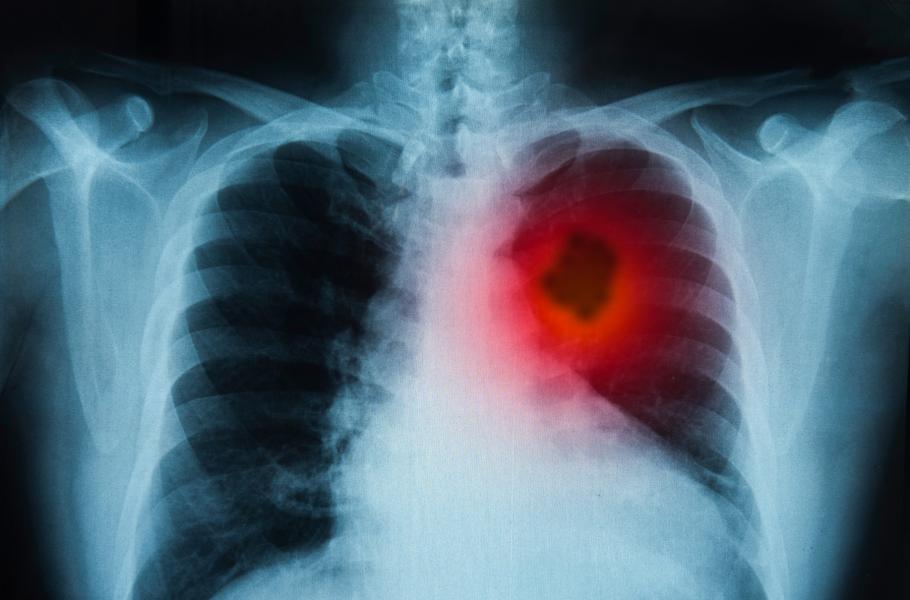

Vlad prodělal všechny dostupné typy léčby. Podrobil se chemoterapii i ozařování. Jeho nádory však měly tuhý kořínek a vzdorovaly všemu. Lékaři přiznali, že vyčerpali poslední možnosti. Pro Vlada už mohou udělat jediné – zajistit mu důstojné umírání s co nejmenším utrpením.

Pro Joa, Elen a Vlada představovala poslední šanci vakcína tvořená bílkovinou produkovanou nádorovými buňkami. Pokud by se podařilo podat Vladovi bílkovinu tak, aby její přítomnost zaznamenal jeho imunitní systém, mohlo by se pacientovo tělo začít proti zhoubnému nádoru bránit. Zničilo by některé nádorové buňky a jejich obsah by se vylil. Tím se buňkám imunitního systému zpřístupní další molekuly typické pro Vladův nádor a bílé krvinky na rakovinu zaútočí v druhém sledu.

Vladovi bylo stále hůř. Nádorové buňky pronikly do mozku a ochromily ho. Jo a Elen už nemohli dál čekat. Nakoupili vše potřebné, pronajmuli laboratoř a jako laici se pokusili připravit vakcínu. „Není to jednoduché a neříkám, že to může dělat kdokoli. Ale zase to není nějaká kosmická věda,“ říká Jo. „Když opravdu chcete, tak to zvládnete.“